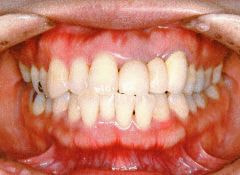

治療例2 (補綴処置+矯正)